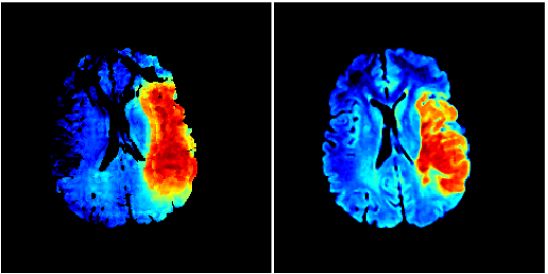

Multi-Center

Prediction of Hemorrhagic Transformation in Acute Ischemic Stroke

using Permeability Imaging Features. F. Scalzo, J. Alger, X. Hu,

J. Saver, K. Dani, K. Muir, A. Demchuk, S. Coutts, M. Luby,

S. Warach, D. Liebeskind. Magn Reson Imaging. 1(6):961-9, 2013.

Regional Prediction of Tissue Fate in Acute Ischemic Stroke.

F. Scalzo, Q. Hao, X. Hu, and D. Liebeskind. Annals of Biomedical

Engineering. in press, 2012. |